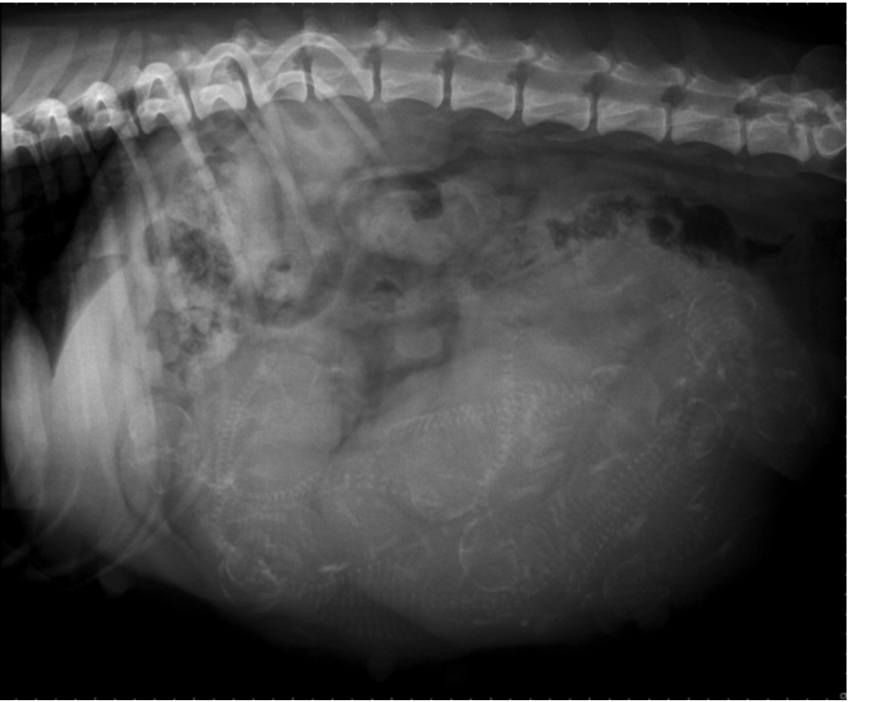

sissi Q Röntgen